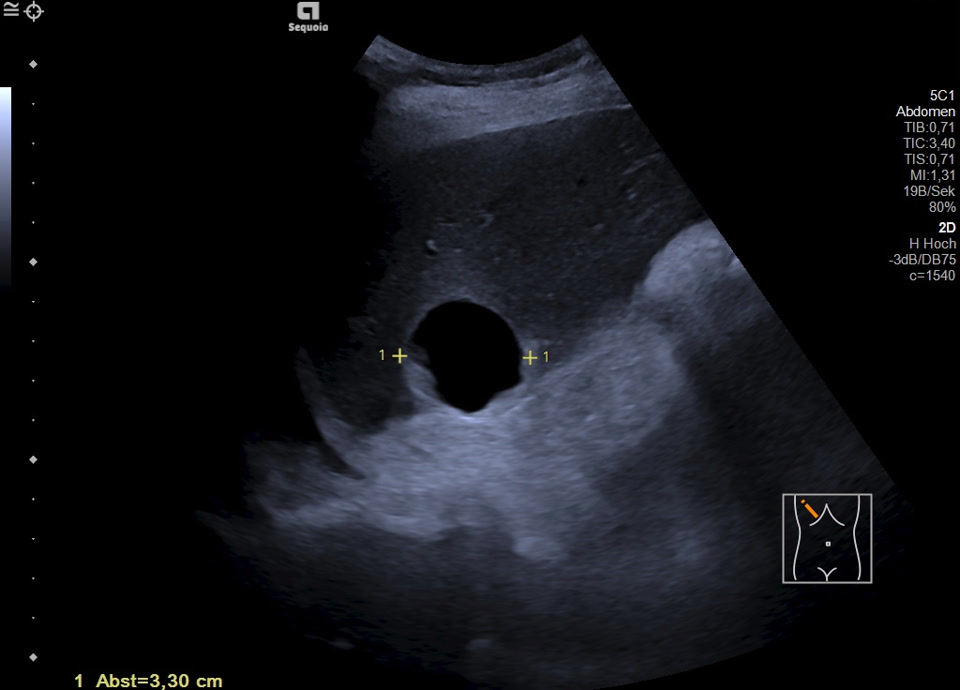

Es zeigt sich subkapsulär in Segment VI der Leber eine zystische Raumforderung mit durchgehendem Kapselreflex und hyperechogenem solidem Anteil. Der Befund ist nicht vereinbar mit einer blanden Zyste, sondern suspekt auf eine zystisch-solide Metastase. In der ergänzenden CEUS nehmen die soliden Anteile in der arteriellen Phase Kontrastmittel auf und zeigen in den portalvenösen sowie späten Phasen eine persistierende KM-Anreicherung ohne Washout. Zusätzlich finden sich eine noduläre Peritonealverdickung im Oberbauch sowie ein zystischer Ovarialtumor mit soliden Anteilen im rechten Unterbauch. In Zusammenschau der Befunde besteht der dringende Verdacht auf ein hepatisch und peritoneal metastasierendes Ovarialkarzinom.